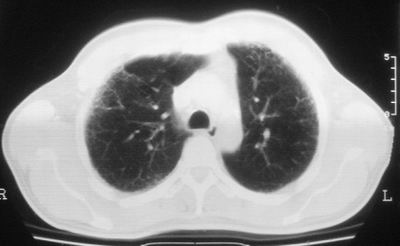

双肺散在小结节影,考虑粟粒性肺结核.肺窗薄扫会更好看些.

考虑粟粒性肺结核

双肺外侧带胸膜下可见网状阴影,考虑轻度肺间质纤维化。

就这图像考虑间质性肺炎。